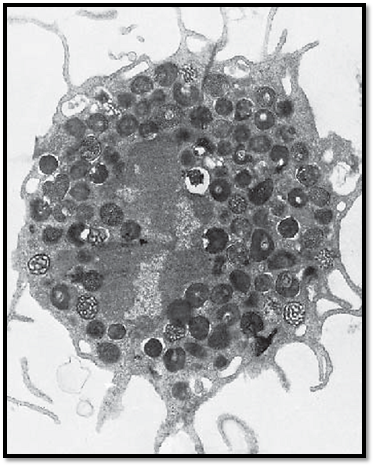

This transmission electron microscopic image displays the typical ultrastructure of a tissue mast cell from a rat. On the surface are sporadic short plasma membrane processes. The central nucleus is relatively small and shows peripheral heterochromatin. The nucleus is dente d in several places because of the close vicinity to cell-specific granules. The cytoplasm contains the specific round or oval granules, which have diameters of about 0.5–1.5 μm. The granules are always enclose d by a membrane and separate d from other granules by cytoplasmic septa, which contain crista-type mitochondria, Golgi complexes and, sporadically, filaments. The matrix of each granule is homogeneous and electron-dense. Based on their sulfate d glycosaminoglycan content, mast cells show a meta-chromatic reaction—i.e., their granules appear between blue-violet and re d after staining with a blue alkaline thiazine dye. The granules contain heparin and the biogenic amine histamine. Heparin inhibits blood clotting and is a potent anticoagulant. Histamine causes the arteries and arterioles in connective tissue to dilate. There are two different types of mast cells—the tissue mast cells in the connective tissue of the skin and the mucosa mast cells in the connective tissue of mucous membranes.

Electron microscopy; magnification: × 11400